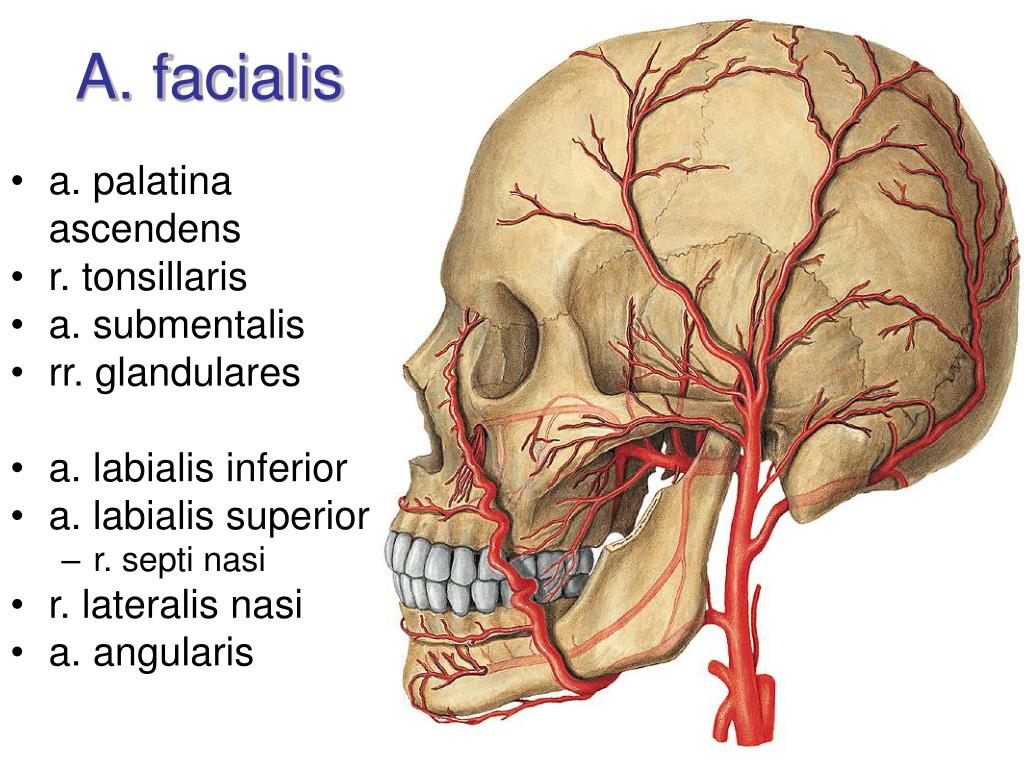

Анатомические изображения срединной сагиттальной линии черепа